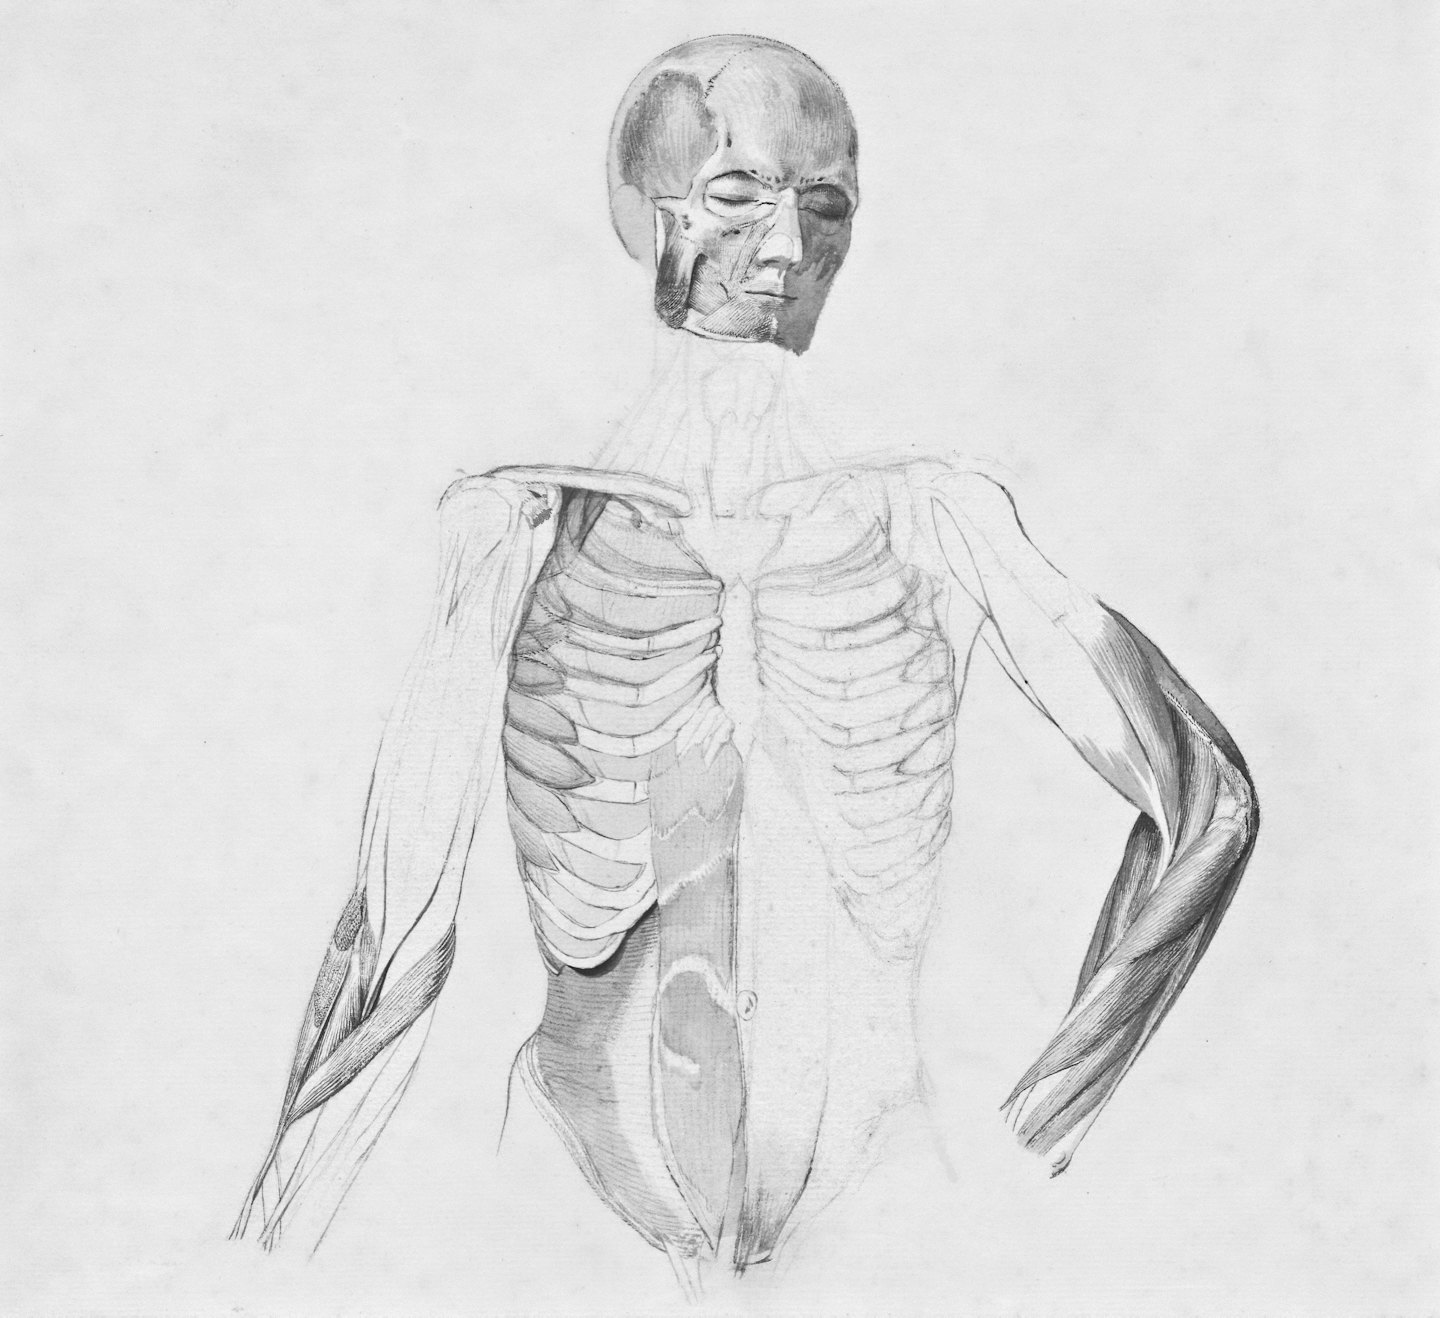

El desarrollo de unos brazos masivos y funcionales depende de la manipulación precisa de los momentos de fuerza. En este análisis de ingeniería, diseccionamos la biomecánica de flexión y extensión de codo para asegurar que cada grado de movimiento genere la máxima tensión mecánica, protegiendo siempre la salud de tus tendones.

Aquí analizamos detalladamente la biomecánica de los brazos, mostrando cómo optimizar la hipertrofia de bíceps y tríceps con precisión científica.

Protección Tendinosa

Estrategias para fortalecer tendones y prevenir lesiones durante el entrenamiento intenso.

Estudio detallado de la flexión y extensión del codo para mejorar la función muscular.

Aprende cómo manipular momentos de fuerza para maximizar la flexión de codo.

Descubre estrategias para mejorar la extensión del codo y proteger tendones.

Aquí encontrarás imágenes que ilustran la biomecánica y técnica para maximizar la hipertrofia muscular.